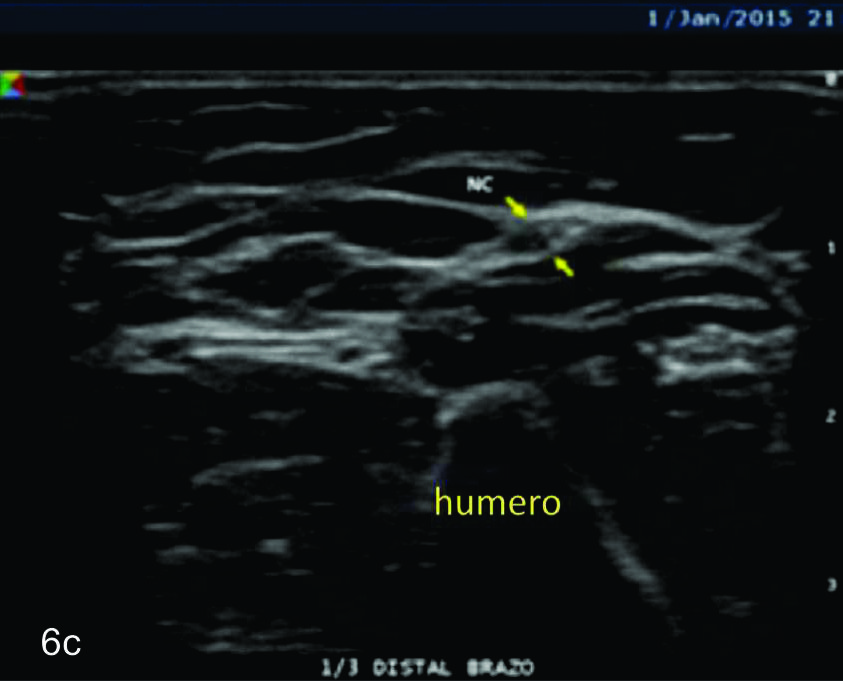

Figura 6

Nervio cubital

B- tercio medio del brazo,

C- tercio distal del brazo,

Figura 7

Serie de cortes axiales del nervio cubital desde su origen a nivel del hueco axilar hasta su terminación a nivel del canal de Guyon. Se identifica el mismo señalado por flechas amarillas y con las letras NC. AH-arteria humeral, PC- músculo prondador cuadrado, P- hueso pisciforme, Línea roja- ligamento anular del carpo, Línea amarilla- túnel de Guyon, Flecha azul- Arteria cubital-. A-tercio distal antebrazo, B- canal de Guyon.